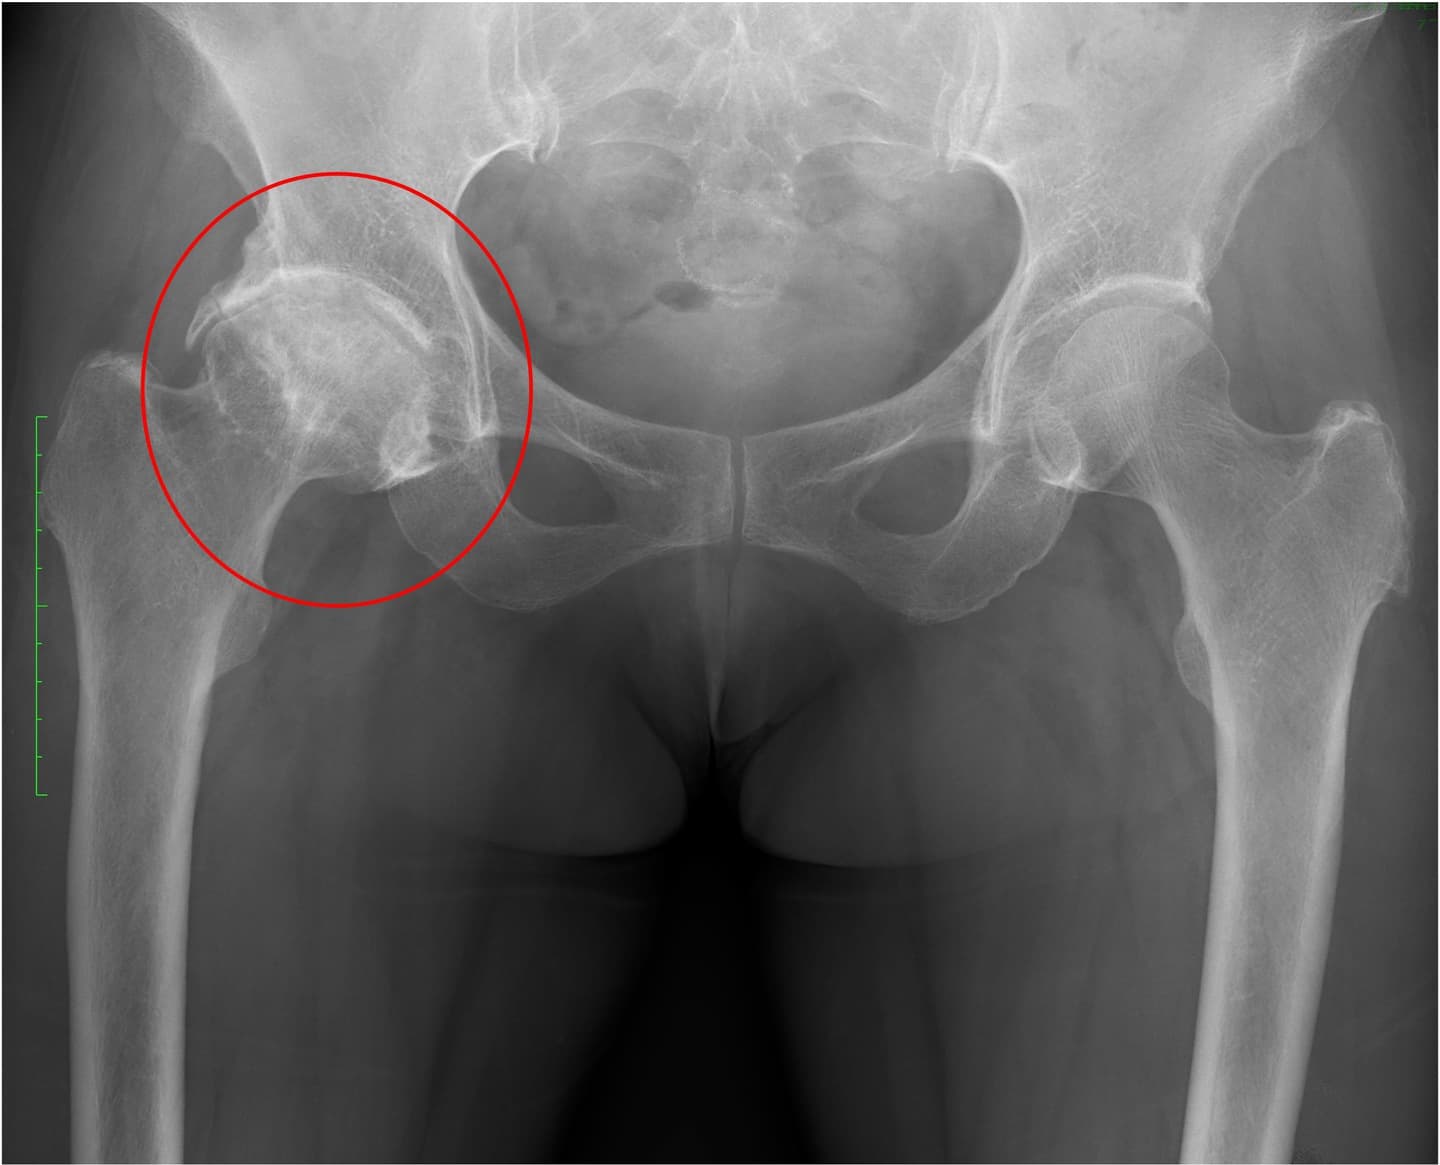

手術の1年半前より右股関節痛が出現し、徐々に歩行時痛は増強し夜間も右股関節〜大腿部へ疼くような疼痛も出現、術前は疼痛による右下肢への荷重困難と股関節の可動域制限、筋力低下により屋内では壁伝いで7m程度、屋外では足を引きずる形で10分程度の歩行耐久性でした(動画)。また足が開きにくいことで靴下の着脱や足の爪切り動作の困難感がみられました。近医での治療行うも症状改善なく当院へ2023年3月受診され、右変形性股関節症の診断あり同年5月に右人工股関節置換術が行われました。